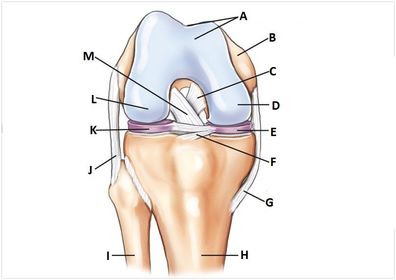

A. patellar surface B. femur C. PCL D. medial condyle E. medial meniscus F. transverse ligament G. tibial medial collateral ligament (MCL) H. tibia I. fibula J. fibular lateral collateral ligament (LCL) K. lateral meniscus L. lateral condyle M. ACL